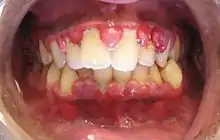

Gingival enlargement can be a feature in some periodontal diseases. | |